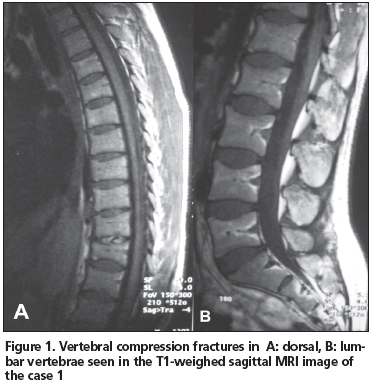

Twenty-six years old female patient was admitted to our rheumatology out-patient clinic with the complaint of low back pain. Her pain started 4 months ago, immediately after delivery of her first child. The pain was aggravated by physical activity and diminished with nonsteroidal antiinflamatory drugs. Lumbar MRI was carried out with the prediagnosis of lumbar disc herniation. Vertebral deformities due to compression fractures were discovered both in the dorsal and lumbar vertabrae (Figure 2), and the patient was hospitalized for differential diagnosis.